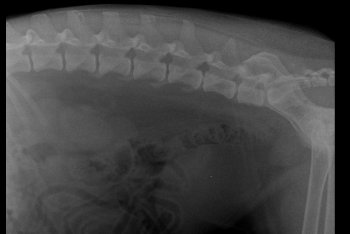

Garret Posted March 14, 2019 Share Posted March 14, 2019 Hi Guys, My dog has been diagnosed with IVDD since February 2nd of 2019. Im at a lost to treat him, please help. So far Im taking him for acupuncture 2x a week. He is being medicated with Analsik 2x a day, and I apply Glucosamine Gel over his joints. Since he has a hard time walking I'm trying to learn to express bladder him, but pooping is still something I can't figure out how to help him does it. So far my vet has diagnosed him with IVDD from looking at his Xray. But there is something that me and my doctor are not sure about which is the Xray on his neck, regarding what is near the AXIS of his neck. I don't know where to ask to next.. I have consulted with 5 vets and not one of them seems to be able to give a definite answer. Some say its a piece of the fracture that broke off, other speculate that it might be cancer. I'm really scared for my dog, and if anyone could help tell me more on what exactly is happening to my dog's neck. or at least point me where I could better ask these questions would help a lot! Link to comment Share on other sites More sharing options...